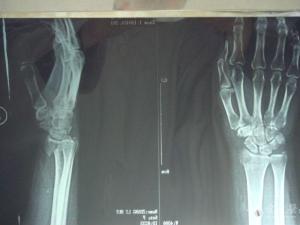

桡骨远端关节面纵斜向断裂、伴有腕关节半脱位者称为Barton骨折,又称巴顿骨折、巴尔通骨折。[1]